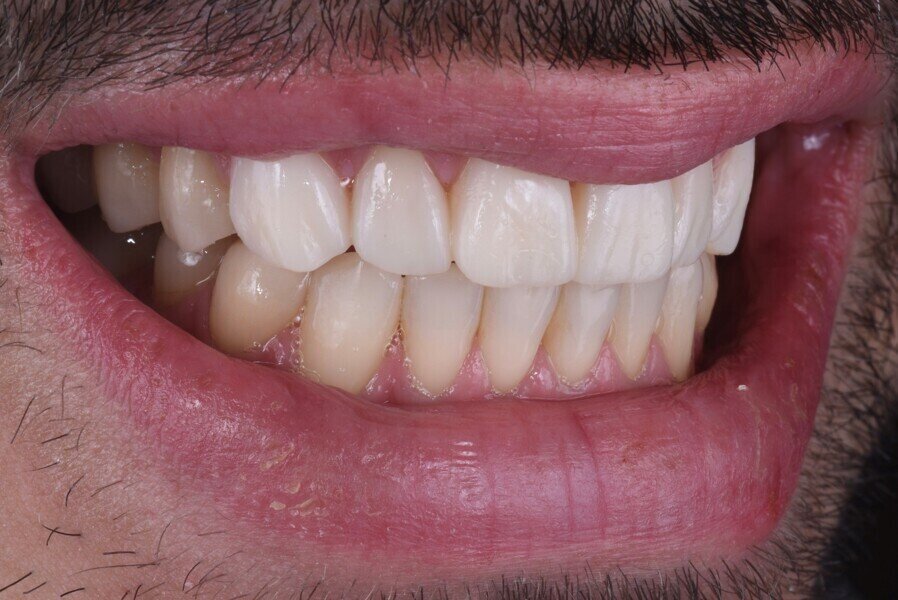

Nakonec byly finální korunkové náhrady (obr. 14) adhezivně fixovány v ústech za izolace kofferdamem (obr. 15). Pacient byl sledován několik týdnů po cementaci náhrad (obr. 16 a 17).

Obr. 16a: Závěrečná extraorální fotografie.

Obr. 16b: Závěrečná extraorální fotografie.

Obr. 17a–c: Finální intraorální fotografie.